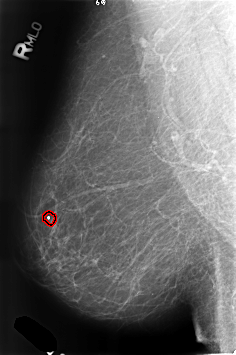

B_3250_1.RIGHT_MLO

RIGHT_CC LINES 4568 PIXELS_PER_LINE 3080 BITS_PER_PIXEL 12 RESOLUTION 50 OVERLAY

RIGHT_MLO LINES 4608 PIXELS_PER_LINE 3056 BITS_PER_PIXEL 12 RESOLUTION 50 OVERLAY

FILE: B_3250_1.RIGHT_MLO.OVERLAY

TOTAL_ABNORMALITIES 1

ABNORMALITY 1

LESION_TYPE CALCIFICATION TYPE LUCENT_CENTER DISTRIBUTION N/A

ASSESSMENT 2

SUBTLETY 5

PATHOLOGY BENIGN_WITHOUT_CALLBACK

TOTAL_OUTLINES 1

BOUNDARY